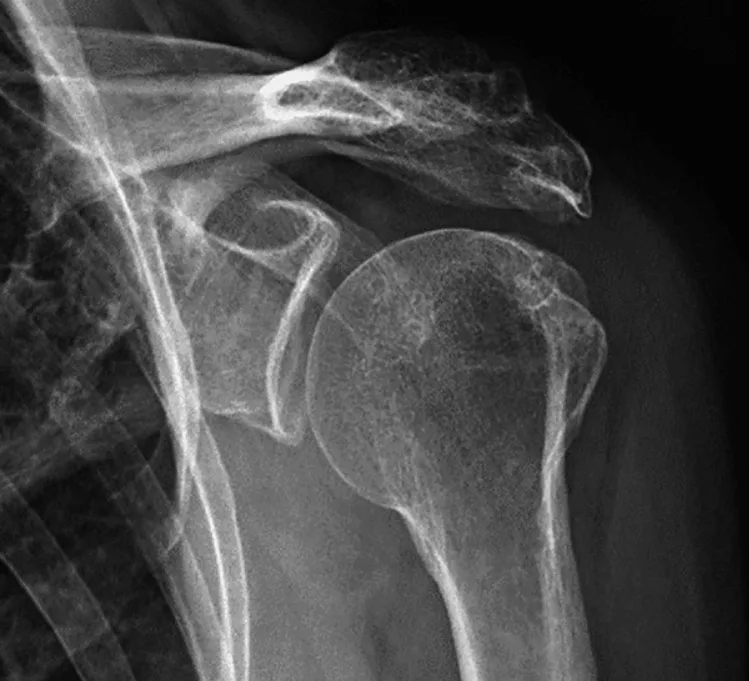

O diagnóstico da artrose acromioclavicular é geralmente realizado por um especialista em ombro, como um ortopedista. Durante o exame físico, o médico procurará sinais de inchaço, sensibilidade e crepitação na área do ombro. Radiografias e ressonâncias magnéticas também podem ser solicitadas para avaliar a gravidade da condição e descartar outras lesões no ombro.

Conhecida também como osteoartrite das articulações acromioclaviculares, é uma artrose caracterizada pelo desgaste da articulação entre o acrômio (parte do osso escapular) e a clavícula. Essa condição é comumente causada por atividades físicas intensas ou esportes que envolvem movimentos repetitivos do ombro. A artrite acromioclavicular pode levar a alterações ósseas, que podem causar danos aos tendões e à cápsula articular do ombro.